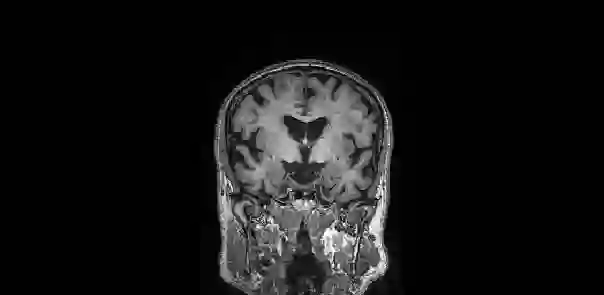

In human neuroimaging studies, atlas registration enables mapping MRI scans to a common coordinate frame, which is necessary to aggregate data from multiple subjects. Machine learning registration methods have achieved excellent speed and accuracy but lack interpretability. More recently, keypoint-based methods have been proposed to tackle this issue, but their accuracy is still subpar, particularly when fitting nonlinear transforms. Here we propose Registration by Regression (RbR), a novel atlas registration framework that is highly robust and flexible, conceptually simple, and can be trained with cheaply obtained data. RbR predicts the (x,y,z) atlas coordinates for every voxel of the input scan (i.e., every voxel is a keypoint), and then uses closed-form expressions to quickly fit transforms using a wide array of possible deformation models, including affine and nonlinear (e.g., Bspline, Demons, invertible diffeomorphic models, etc.). Robustness is provided by the large number of voxels informing the registration and can be further increased by robust estimators like RANSAC. Experiments on independent public datasets show that RbR yields more accurate registration than competing keypoint approaches, while providing full control of the deformation model.